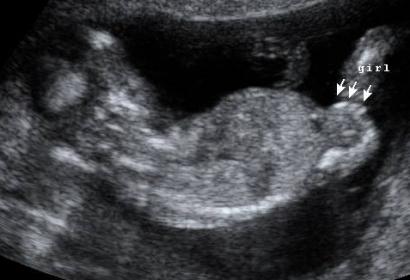

The private tech I saw at 14 weeks was very good and said I had a "textbook girl." At 18 weeks, if the baby was a boy, would the tech be able to see the boy bits clearly on a scan? I'm still feeling confident the private tech was right and this last one was just a complete ding-a-ling, but I guess I'm feeling a little nervous now... Opinions would be appreciated. Thanks.